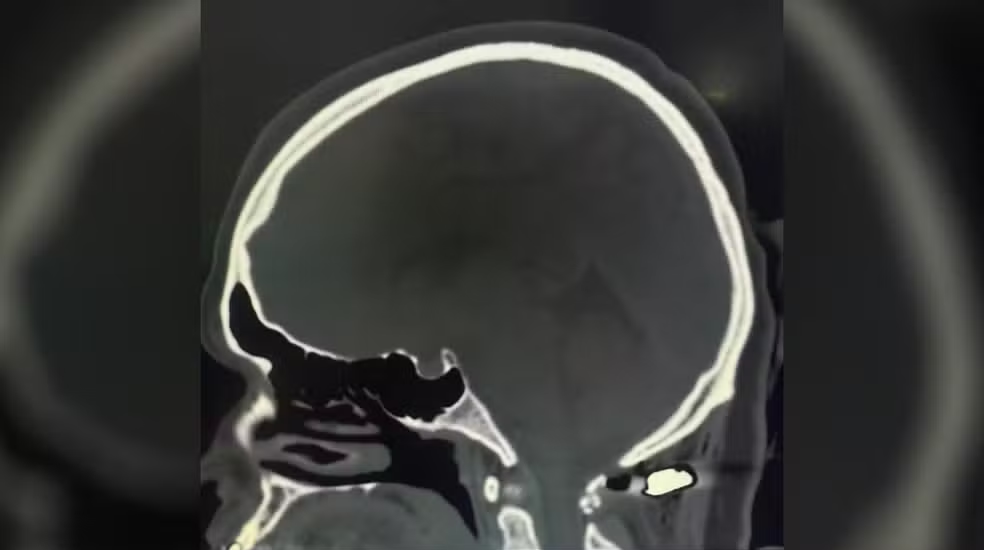

Foi a equipe de neurocirurgia, liderada pelo Dr. Felipe Salvagni Pereira, quem revelou a extensão da sorte de Juliete. A tomografia computadorizada do crânio e da coluna cervical mostrou o projétil alojado em uma posição extremamente delicada. O Dr. Pereira, com sua vasta experiência, ficou chocado ao medir a distância exata entre a bala e a medula cervical. “Quando a gente viu a tomografia, eu tive a curiosidade de medir a distância do projétil para a medula cervical. Uma lesão na medula cervical ou leva a óbito, ou leva à tetraplegia – que é a perda de força nos braços e nas pernas. A distância do projétil até a medula deu 4 milímetros na tomografia, então foi muito perto. Um milagre. É inacreditável que ela esteja tão bem assim”, detalhou o neurocirurgião, expressando seu espanto e alívio.